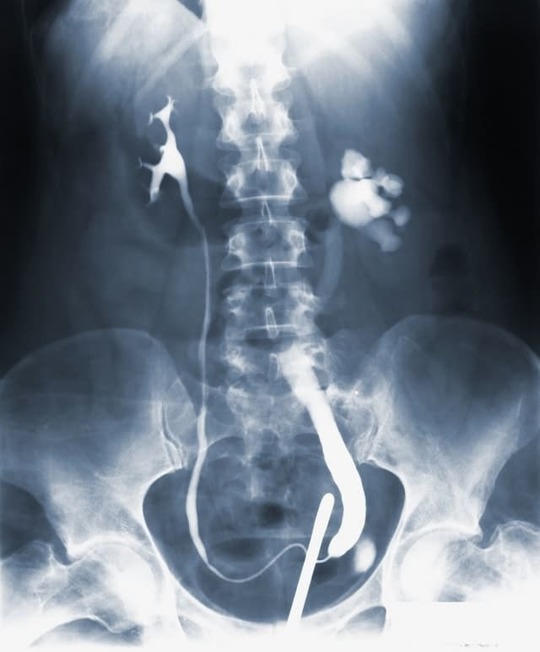

血管型の場合、動脈病変のスクリーニングやβ遮断薬を使って改善を行います。

血管の手術: 血管型EDSの場合、血管の問題に対して外科手術が必要になることがあることもあります。